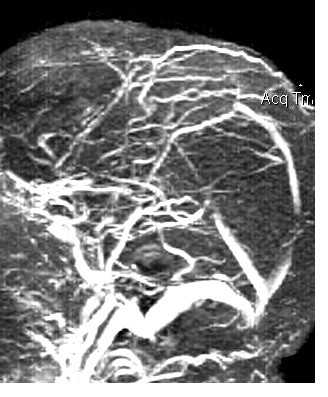

(б) МРТ, постконтрастное Т1-ВИ, режим подавления сигнала от жира, аксиальный срез: у той же пациентки определяется тотальное заполнение интенсивно контрастированной пиальной ангиомой увеличенных извилин конвекситальной поверхности пораженного полушария. (а) МРТ, Т2*SWI, проекция максимальной интенсивности: у той же пациентки определяются расширенные извитые медуллярные вены, расположенные в белом веществе и дренируемые центрально в расширенные субэпендимальные вены.

(б) ЦСА левой внутренней сонной артерии, венозная фаза, боковая проекция: исследование проводилось как часть теста Вада для определения латерализации речи. Определяется недостаточность нормальных кортикальных вен, характеризующихся пролонгированным удержанием контраста вследствие стаза крови в многочисленных расширенных медуллярных венах.